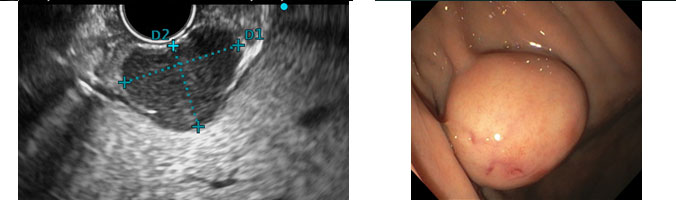

Tumor Gastrointestinal Estromal – GIST

Características ecoendoscópicas

- Origem na segunda ou quarta camada da parede gástrica.

- Geralmente uma massa bem delimitada, hipoecoica e relativamente homogênea.

- Quando maligno: grande tamanho, padrão de eco heterogêneo com focos hiperecogênicos e/ou zonas anecoicas de necrose.

- Borda extraluminal irregular.

- Linfonodomegalias adjacentes com aspecto maligno.

GIST – Sangramento

Imagens Dr. Humberto Schwartz.